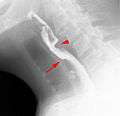

Web with "jet-phenomenon". Arrowhead on incomplete opening of the upper esophageal sphincter.

Esophageal web stenosis in barium swallow examination lateral view.